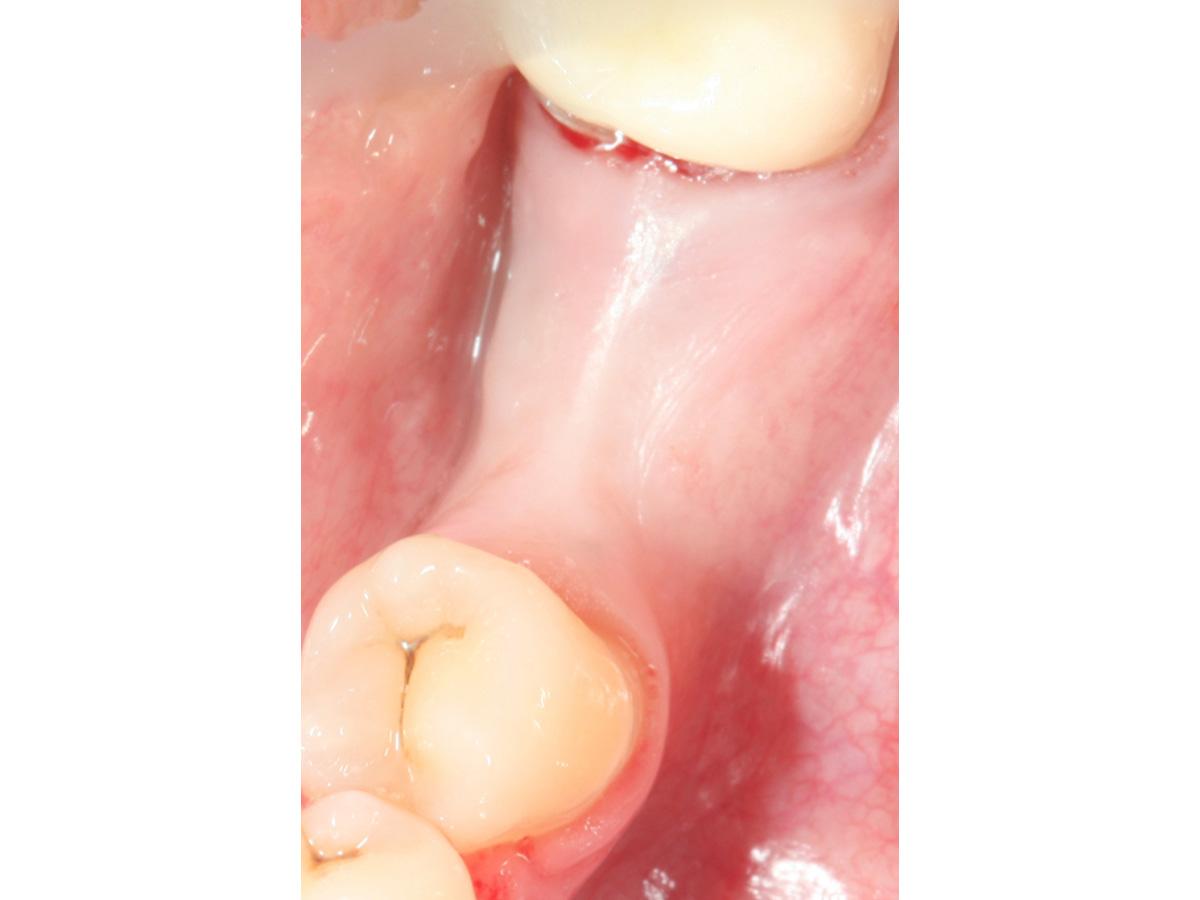

Abb. 8 zeigt die Situation vor dem Freilegen des Implantates und Abb. 9 die erfolgreiche Augmentation fünf Monate post operativ. Zu erkennen sind zwei Pins, deren Position sich im Niveau der Augmentation befinden und damit verdeutlichen, dass es zu keiner Resorption des ursprünglichen Augmentationsniveaus gekommen ist.

Situation vor dem Freilegen des Implantates.

Abbildung 9

Augmentation nach fünf Monaten (klinisch).